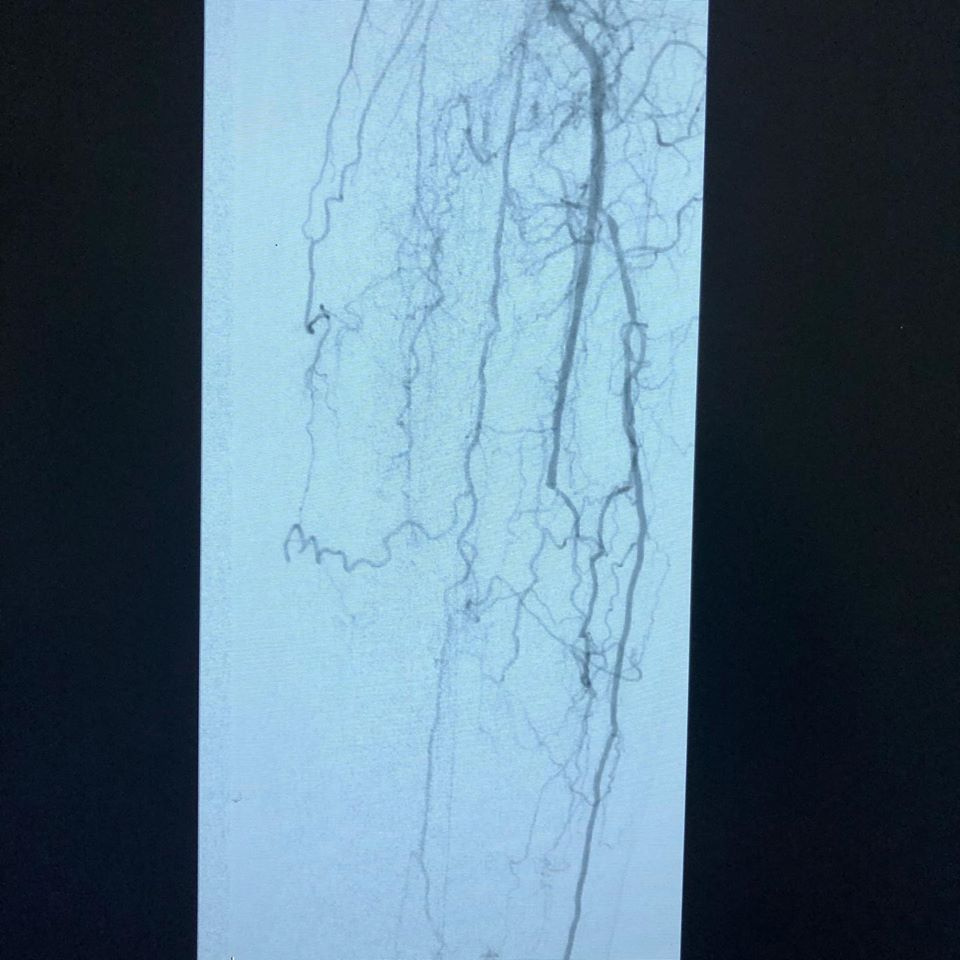

Se pasa a Hemodinamia donde se observa lesiones estenoticas en arteria poplitea y sin vasos tibiales, recanalizando en arteria pedía

(FP2, IP4, P2 GLASS 3) y se realiza angioplastia poplitea y de tibial anterior, mejorando el flujo distal, se realiza amputacion de falange distal del dedo y se observa buena evolución 24 hrs después sin complicaciones con alta a su domicilio